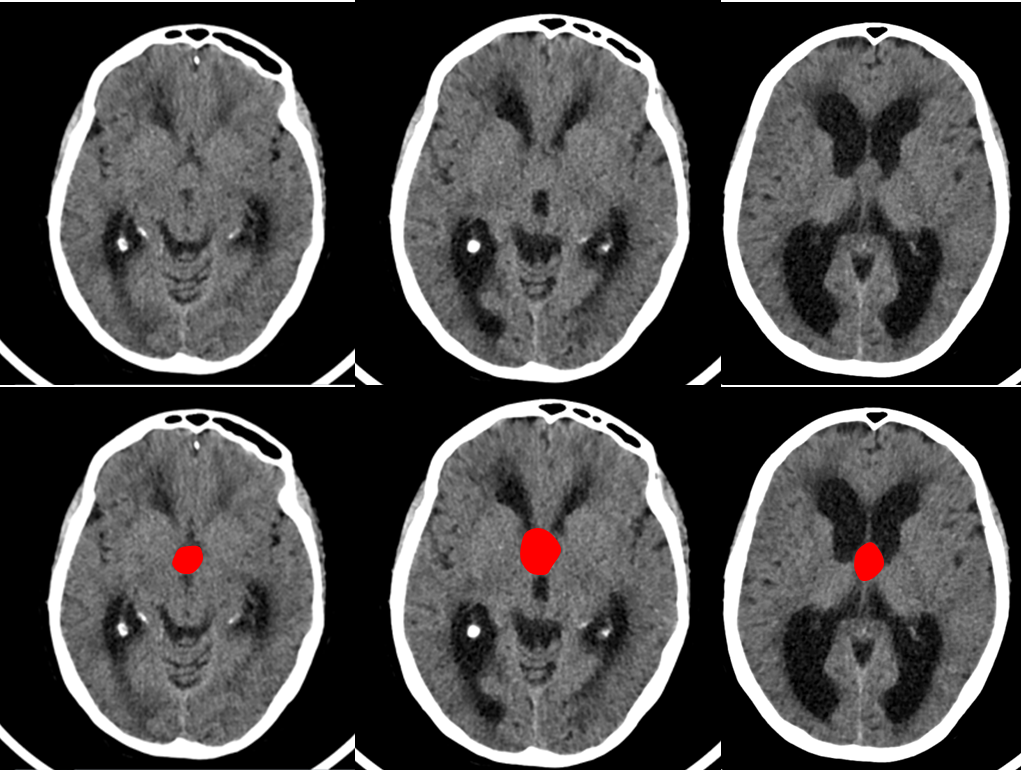

Se trata de un paciente de 63 años que comienza de forma subaguda con torpeza a la marcha y urgencia e incontinencia miccional. Acudió al servicio de urgencias donde se le realizó una TAC cerebral sin contraste (imagen 1 y 2) donde se observaba una hidrocefalia y se derivó a estudio ambulatorio con la sospecha de hidrocefalia normotensiva (imagen 2). La hidrocefalia se produce como consecuencia del aumento del líquido cefalorraquideo en el sistema ventricular cerebral o el espacio subaracnoideo.

La presentación clínica de un quiste coloide del III ventrículo puede ser la misma que la de una hidrocefalia a presión normal (alteración de la marcha, incontinencia urinaria y alteración cognitiva). Los quistes coloides del III ventrículo se suelen ver en la TAC cerebral sin contraste porque en 2/3 de las ocasiones son hiperdensos pero en 1/3 de los casos como éste caso son isodensos/hipodensos y pueden pasar desapercibidos inicialmente. Además hay que tener en cuenta que cuando se introduce contraste en la TAC cerebral puede no verse tampoco. Únicamente tras la realización de la resonancia cerebral se pudo diagnosticar por su hiperintensidad en secuencias T1 (imagen 3) y su hipointensidad en secuencias en T2.

En la imagen 4 se puede intuir la presencia del quiste coloide que inicialmente había pasado desapercibido.